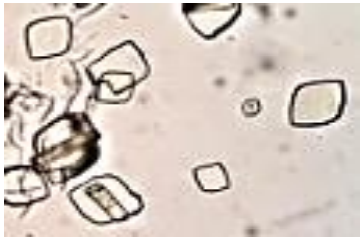

Paciente masculino, 24 anos, sem histórico de doenças prévias, apresenta sintomas de dor intensa durante a micção, dores nas costas irradiando para o baixo ventre e presença de sangue na urina há cinco dias. Ele também menciona que experimentou dores intensas na região dos flancos que se espalharam para o abdome inferior cerca de uma semana atrás. Durante a análise microscópica da amostra da urina do paciente, encontrou-se alguns artefatos, identifique-o:

Figura 2 – Cristais em Urina Tipo I

Assinale a alternativa correta.